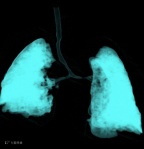

同一患者,CT体积渲染示气管下半部分明显偏向右侧,在左肺动脉异常通过处,气管腔突然变窄,图像如下。